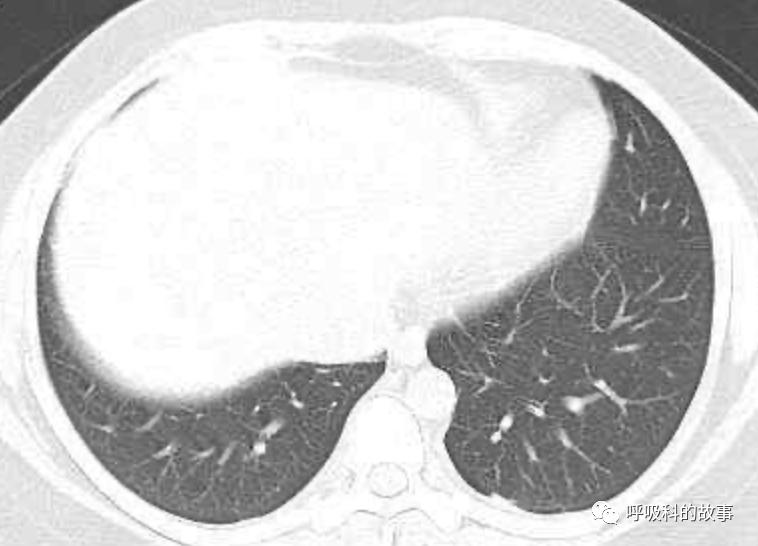

上面三张图分别是第一、二、三周的体温单

患者发热后行胸部CT检查(6月21日,住院第13天),可见两下肺有条片影,当时考虑是肺炎引起的发热。